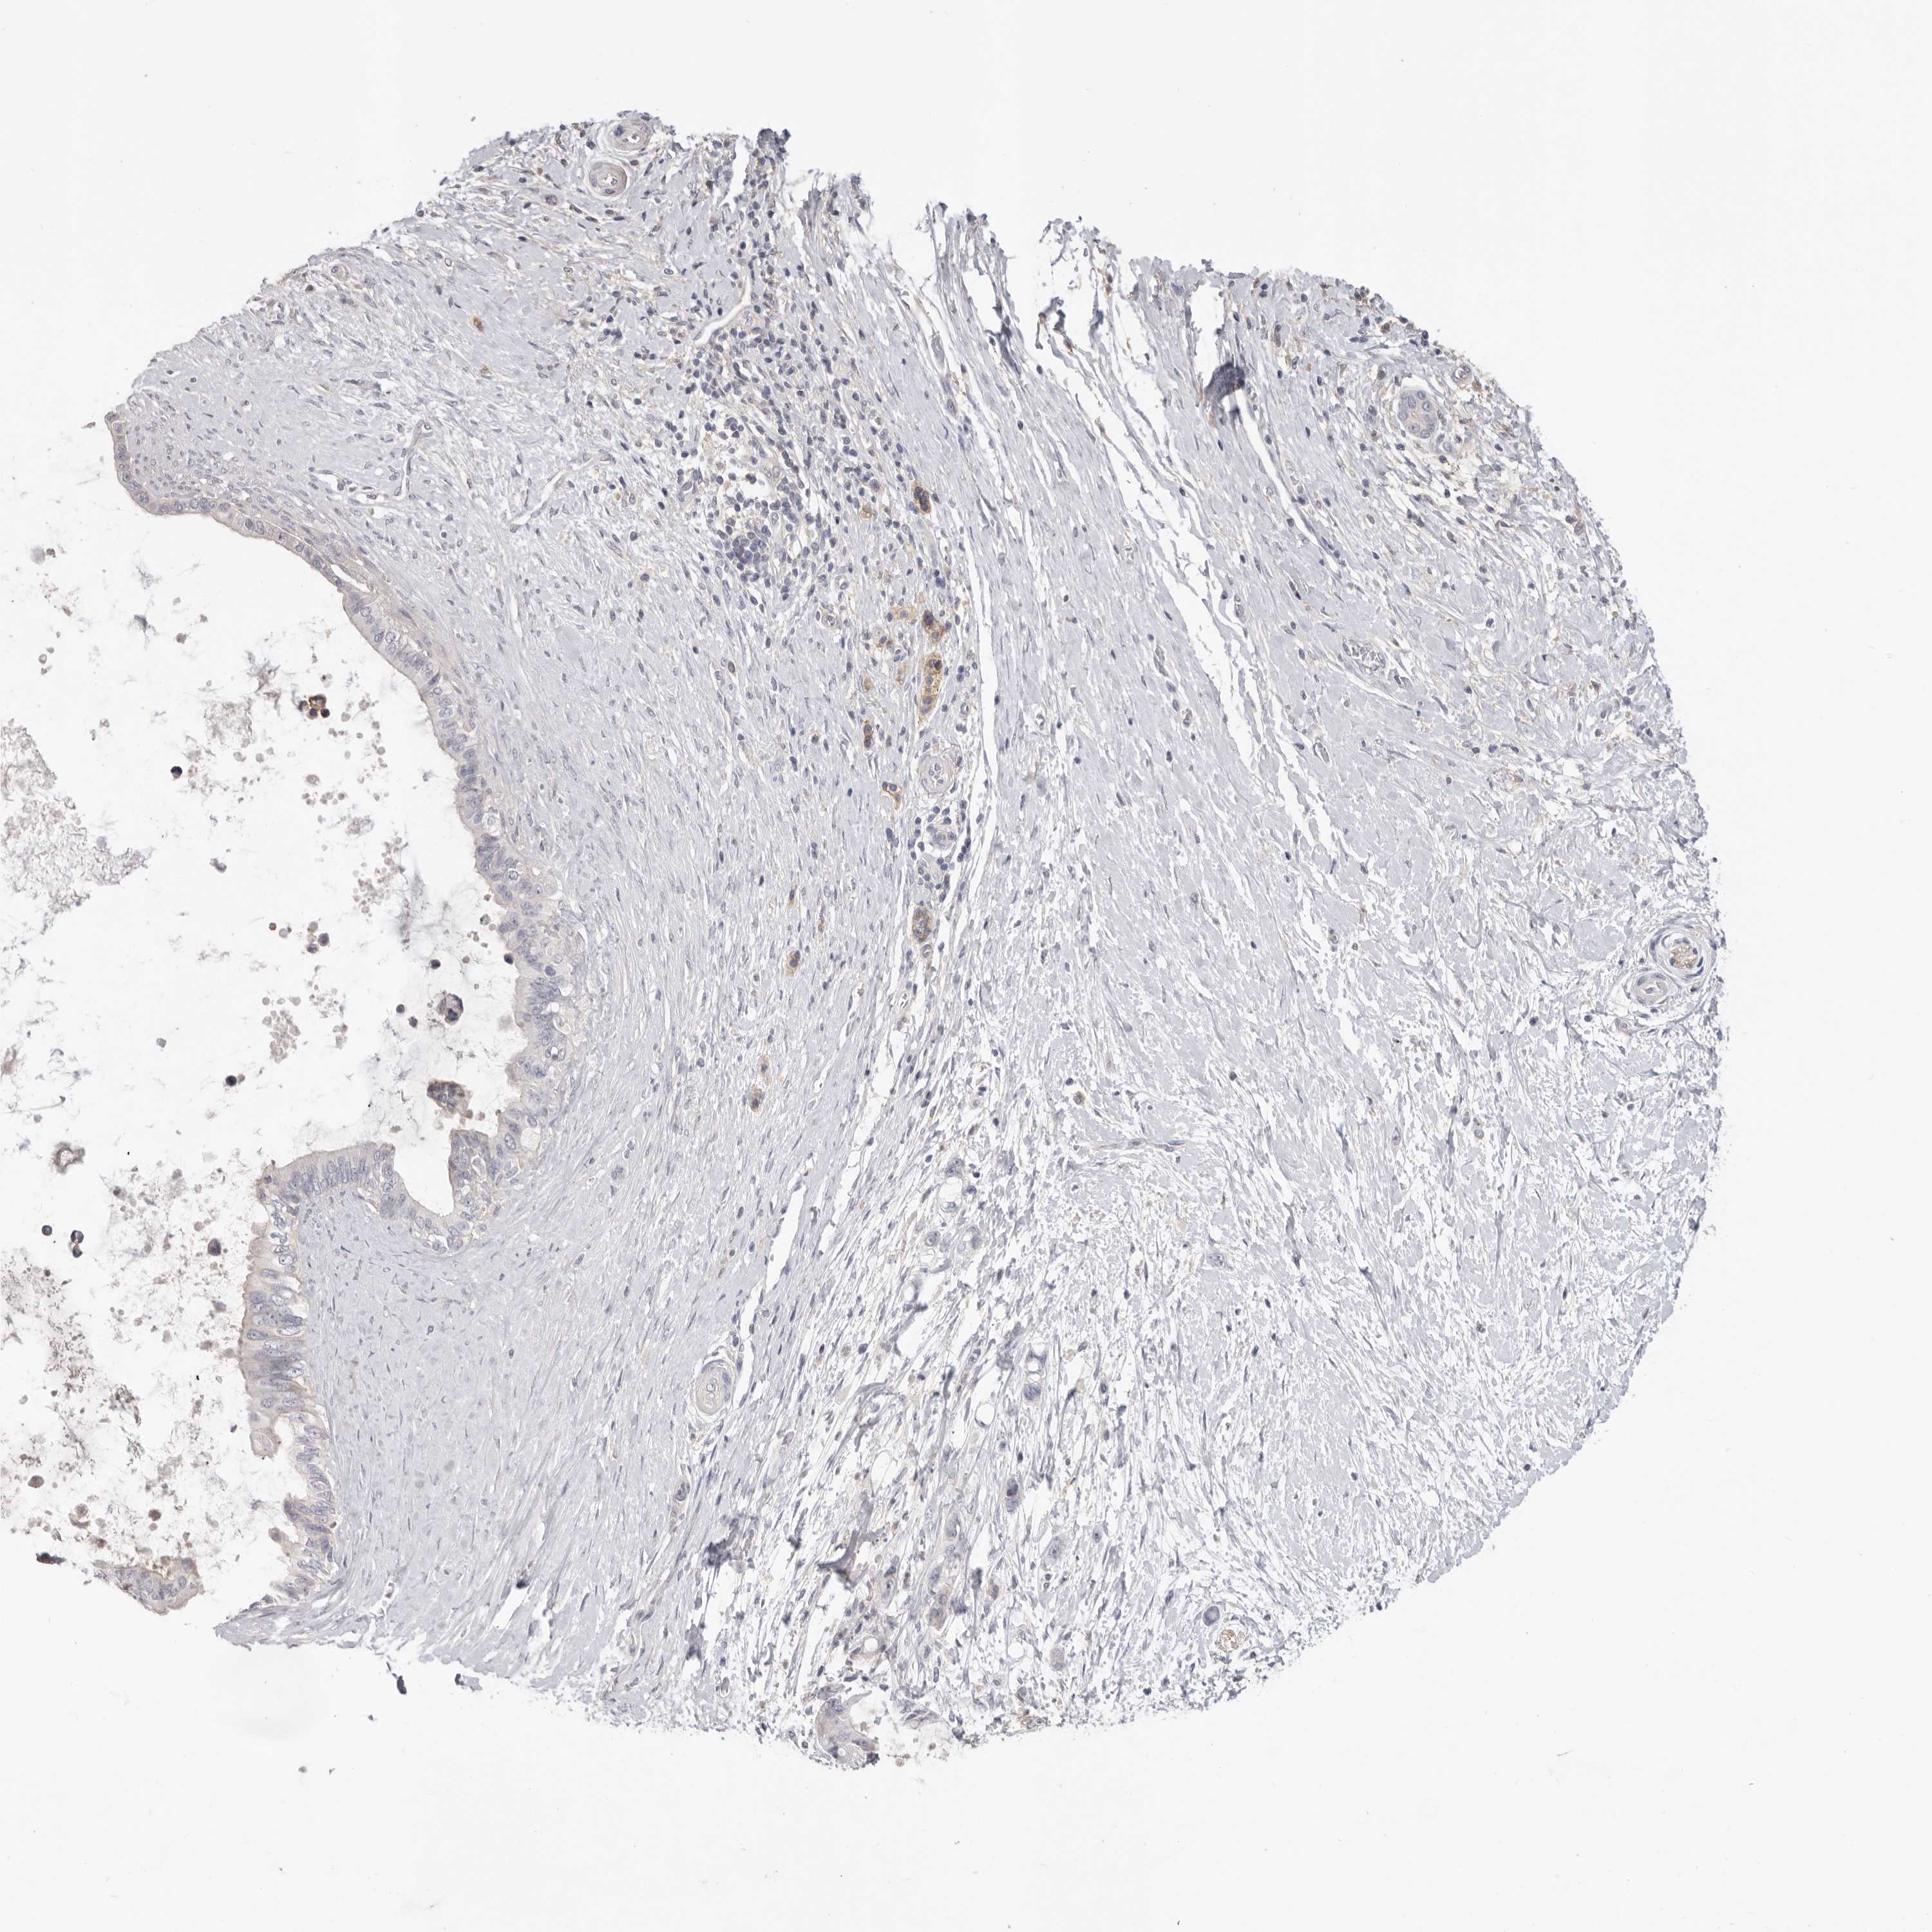

PANCREATIC CANCER - Protein expressioni

A mouse-over function shows sample information and annotation data. Click on an image to view it in a full screen mode. Samples can be filtered based on level of antibody staining by selecting one or several of the following categories: high, medium, low and not detected. The assay and annotation is described here.

Note that samples used for immunohistochemistry by the Human Protein Atlas do not correspond to samples in the TCGA dataset.

Antibody stainingi

Antibody staining in the annotated cell types in the current human tissue is reported as not detected, low, medium, or high, based on conventional immunohistochemistry profiling in selected tissues. This score is based on the combination of the staining intensity and fraction of stained cells.

Each image is clickable and will lead to virtual microscopy that enables deeper exploration of all samples and also displays staining intensity scores, fraction scores and subcellular localization as well as patient and tissue information for each sample.

Antibody HPA028177

Antibody HPA028180

Antibody HPA028182

Staining

High

Medium

Low

Not detected

Intensity

Strong

Moderate

Weak

Negative

Quantity

>75%

75%-25%

<25%

None

Location

Nuclear

Cytoplasmic/membranous

Cytoplasmic/membranous,nuclear

Adenocarcinoma, NOS